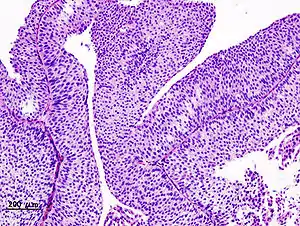

The 1973 WHO grading system for transitional cell carcinomas (papilloma, G1, G2 or G3) is most commonly used despite being superseded by the 2004 WHO[10] grading for papillary types (papillary neoplasm of low malignant potential [PNLMP], low grade, and high grade papillary carcinoma). High-grade carcinoma typically displays more pleomorphism, multiple mitoses, euchromatin and relatively prominent nucleoli, and uneven distribution of nuclei.

Transitional cell carcinoma, being low-grade to the left, and high-grade to the right. H&E stain

Papillary transitional cell carcinoma, low grade